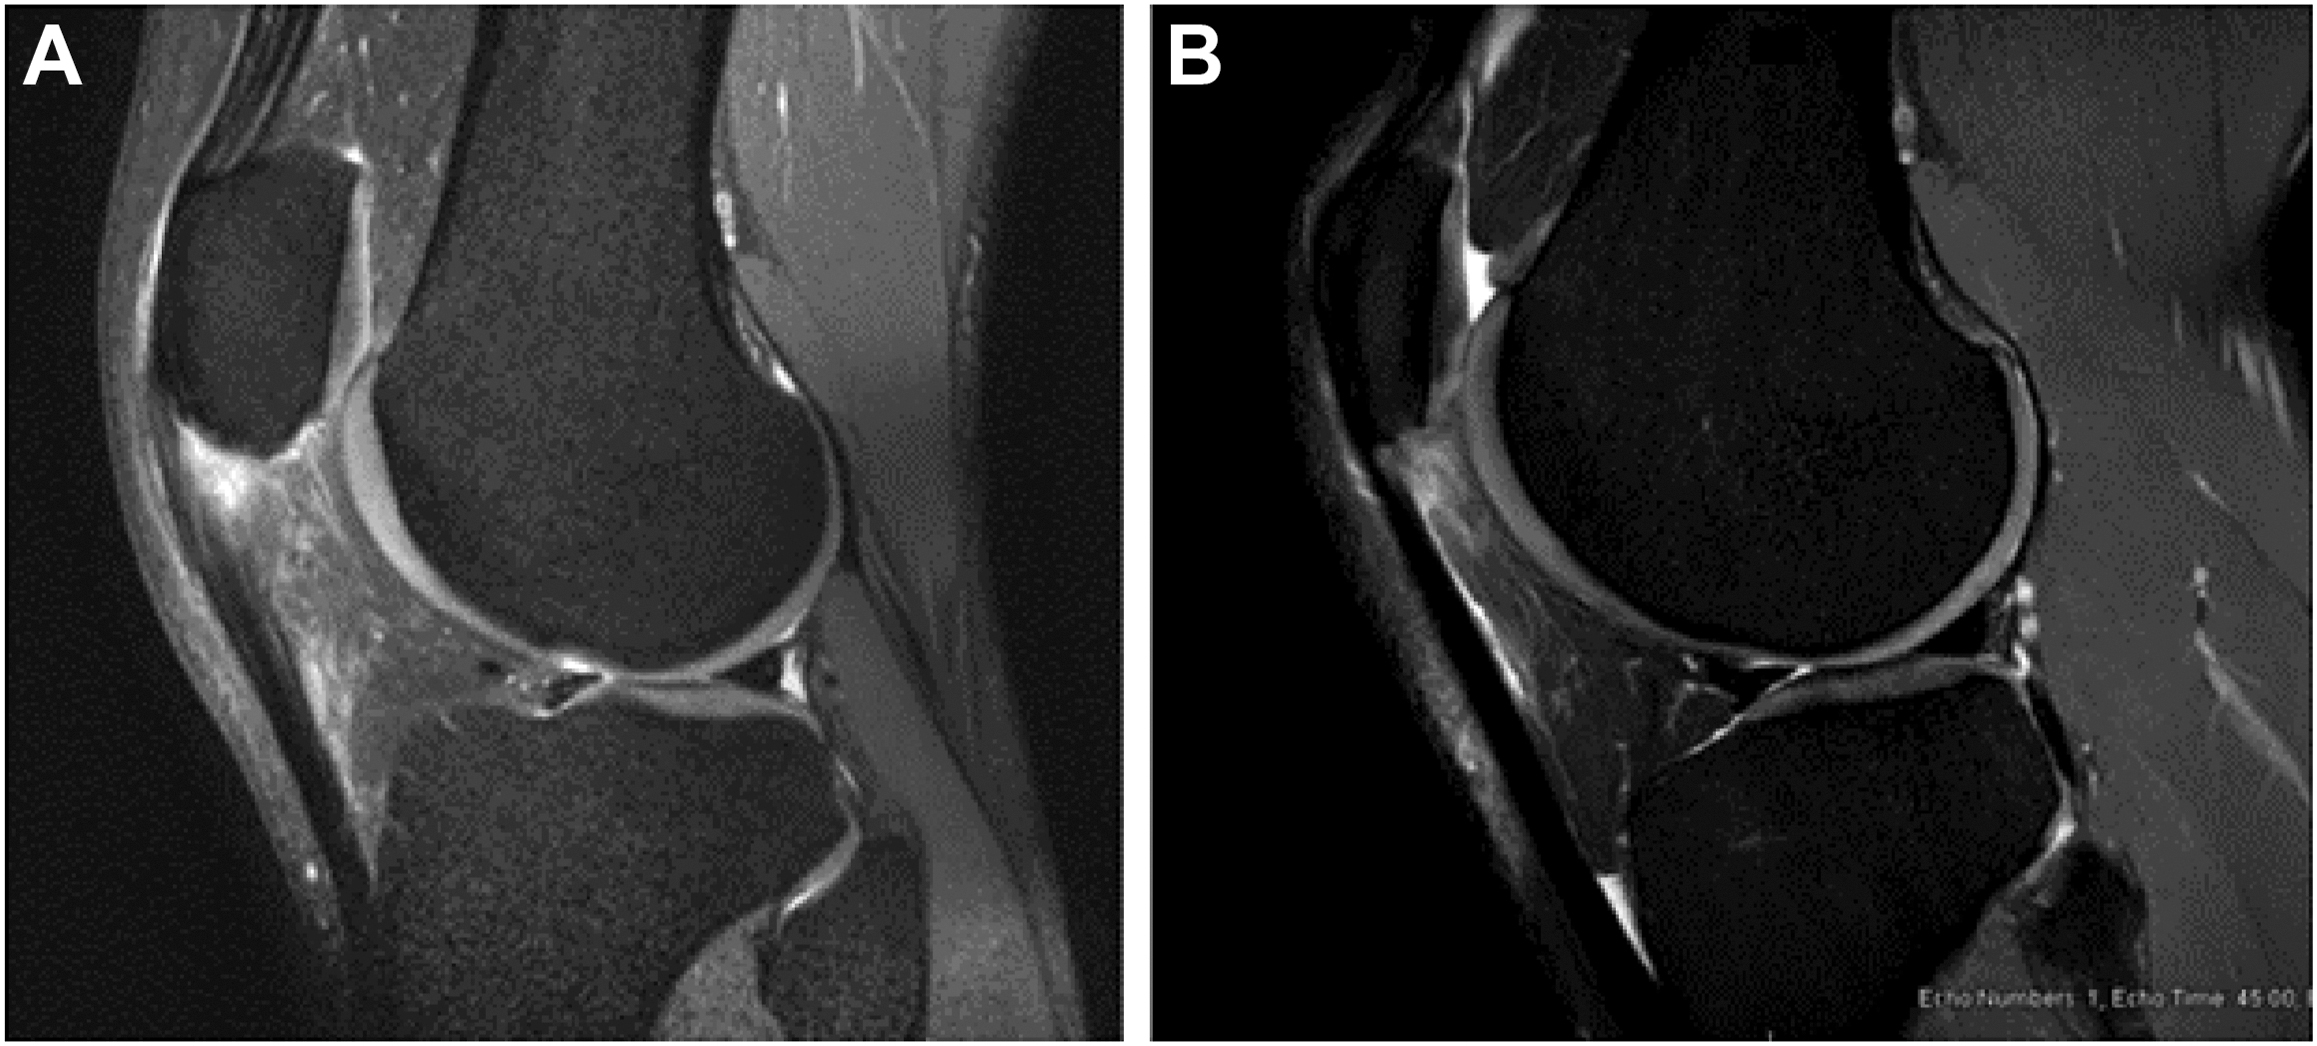

Surgical intervention may include repair ( Fig. 2 ) or meniscectomy. In professional baseball players, lateral meniscus repairs account for 72% of all meniscus repairs. This follows recent recommendations for elite athletes, as it is theorized that the lateral meniscus has better healing potential than the medial meniscus. In the MLB, 74% of players who underwent meniscus repair between 2010 and 2017 returned to sport at an average of 209 days, with 68% returning at the same or higher level of play. There has been no reported difference in return to play rates between lateral and medial meniscus repairs. In this time frame, 19% of MLB players who underwent meniscus repair experienced a second meniscus injury and underwent subsequent meniscectomy within 2 years of their initial repair. Of these players, all but one was able to return to the same level of performance after their subsequent meniscectomy.